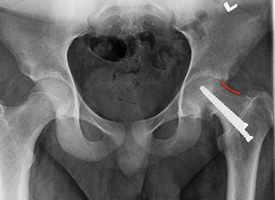

POST OP

The red line demonstrates re-contouring of the femoral neck after arthroscopic treatment. This treatment increases range of motion and prevents further damage to the hip.